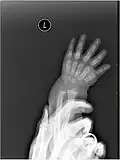

In human anatomy, the metacarpal bones or metacarpus, also known as the "palm bones", are the appendicular bones that form the intermediate part of the hand between the phalanges (fingers) and the carpal bones (wrist bones), which articulate with the forearm. The metacarpal bones are homologous to the metatarsal bones in the foot.

Each metacarpal bone consists of a body or shaft, and two extremities; the head at the distal or digital end (near the fingers), and the base at the proximal or carpal end (close to the wrist).

Fracture

The neck of a metacarpal is a common location for a boxer's fracture, but all parts of the metacarpal bone (including head, body and base) are susceptible to fracture. During their lifetime, 2.5% of individuals will experience at least one metacarpal fracture. Bennett's fracture (base of the thumb) is the most common.[4] Several types of treatment exist ranging from non-operative techniques, with or without immobilization, to operative techniques using closed or open reduction and internal fixation (ORIF). Generally, most fractures showing little or no displacement can be treated successfully without surgery.[5] Intraarticular fracture-dislocations of the metacarpal head or base may require surgical fixation, as fragment displacement affecting the joint surface is rarely tolerated well.[5]